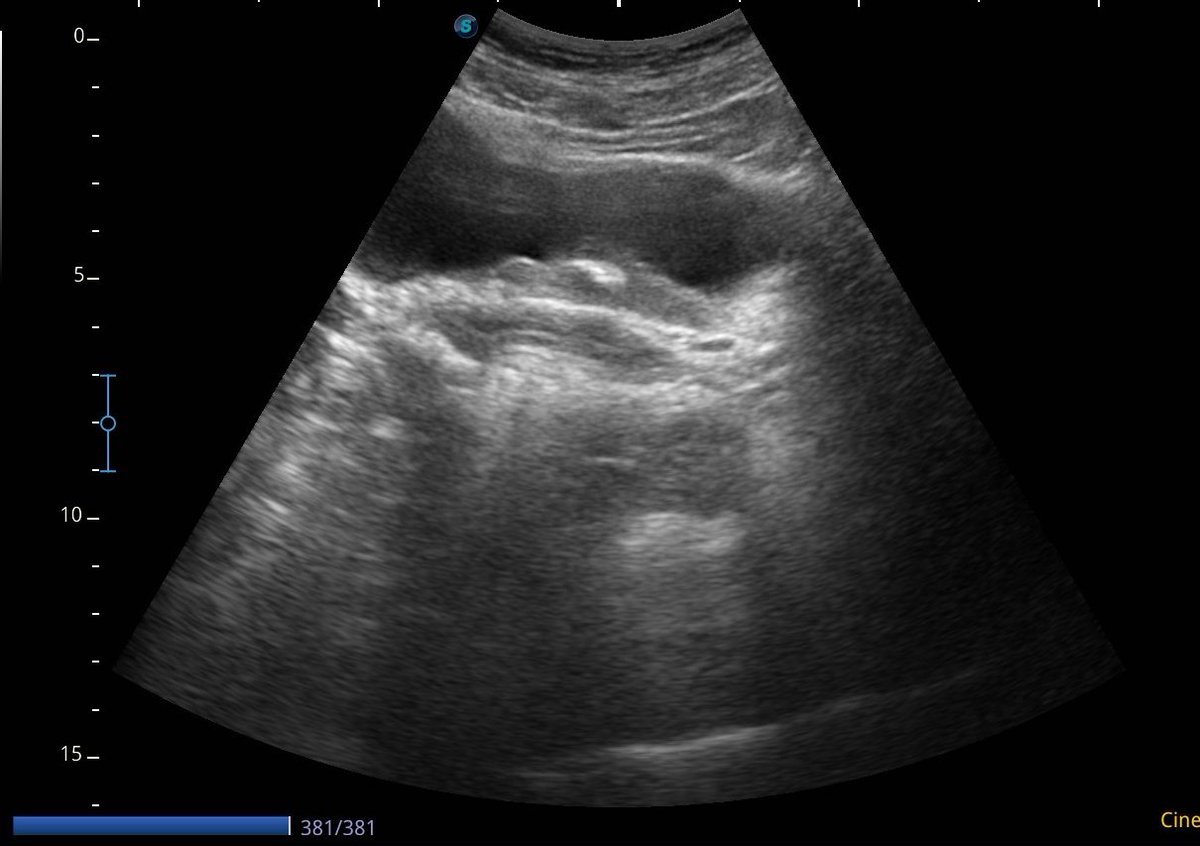

Complete fragmentation of a distal ureteral stone by #ESWL. Radiological and Ultrasound verification. Small stones are also fun!! @FPuigvert @oangerri @koey_kana @paoloverri05 @a_bravo_balado @joanfundi